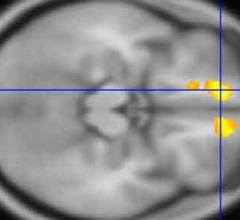

January 9, 2018 — School-age football players with a history of concussion and high impact exposure undergo brain ...